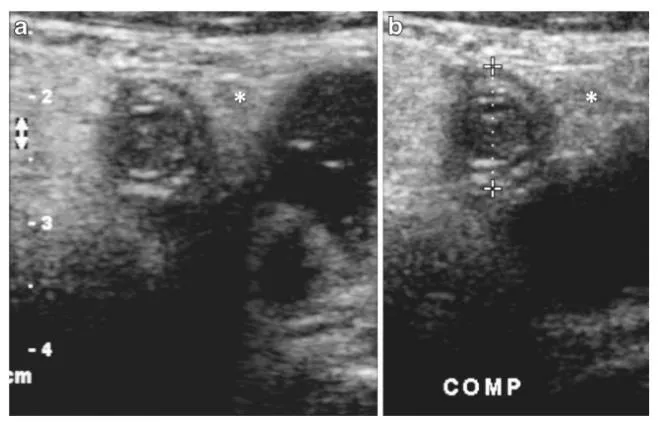

Lack of compressibility

96% 민감도와 특이도